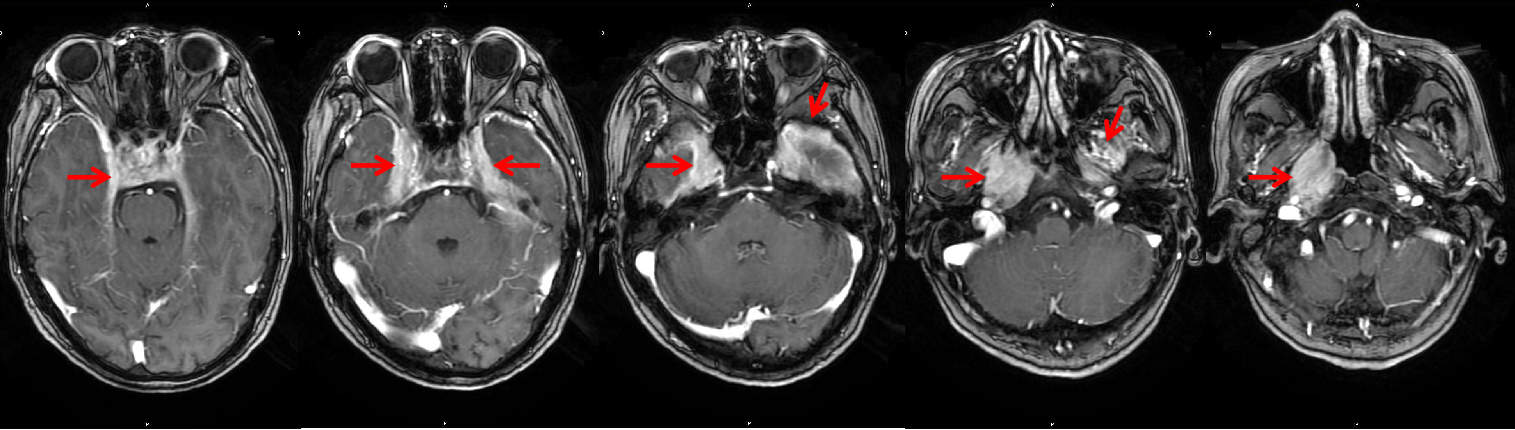

鼻咽癌? 其实是IgG4相关硬化性疾病! ——我院头颈肿瘤MDT团队成功救治一例罕见IgG4相关硬化性疾病患者 关键字:罕见IgG4相关硬化性疾病 2022年4月底,我院放疗科接诊了一...